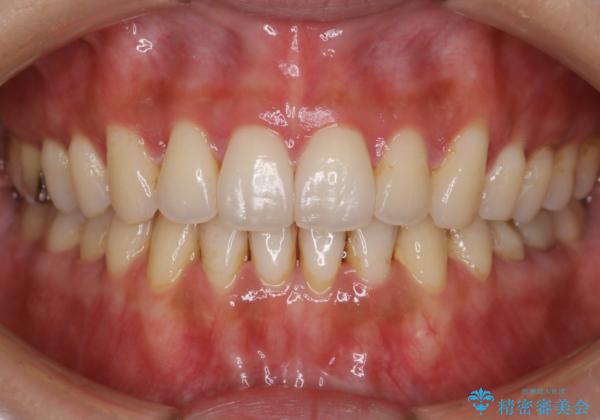

- 歯のガタつきによる見栄えや清掃困難を主訴にご来院されました。

左側の噛み合わせは上の歯が前方に寄ってきてしまっていることが原因のズレがありました。

ガタつき自体は歯列の幅の拡大やディスキング(IPR)でほとんど解消可能でしたが、噛み合わせのズレは歯の移動が必要だったため、左上にマイクロインプラントを使用し噛み合わせの改善とガタつきの解消を同時に進めるという方針をとりました。